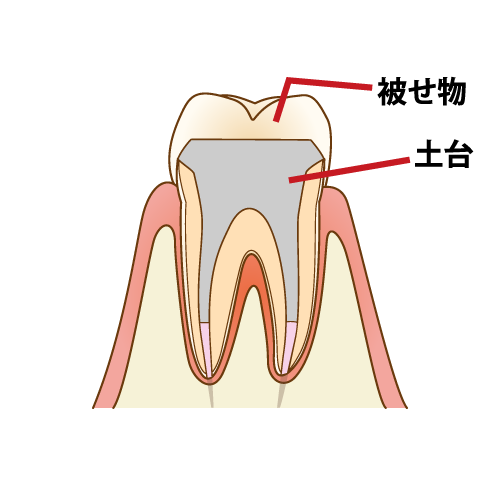

土台作り

治療を行う歯は、度重なる切削によって歯の大部分を失っているため、このまま根管内部に被せ物を装着しても、長期の安定が見込めない場合があります。

そこで、行うのが支台築造(土台の形成)です。歯質を補修したり、歯の根が折れたり割れたり(歯根破折)しにくくして再感染を防ぎます。

まだ虫歯が残っていれば一緒に削り、型取りができるように形を整えます。

被せ物の治療

根管治療を行った歯の虫歯の再発を防ぐには土台の歯と隙間なく適合する精度の高い被せ物をすることが不可欠です。土台の処置がしっかり行われていても、被せ物の精度が低ければ、健康な状態を維持する事は不可能です。耐久性の高い素材の選定をし、精密な被せ物を作製します。

作成した被せ物を装着し、噛み合わせの調整を行います。